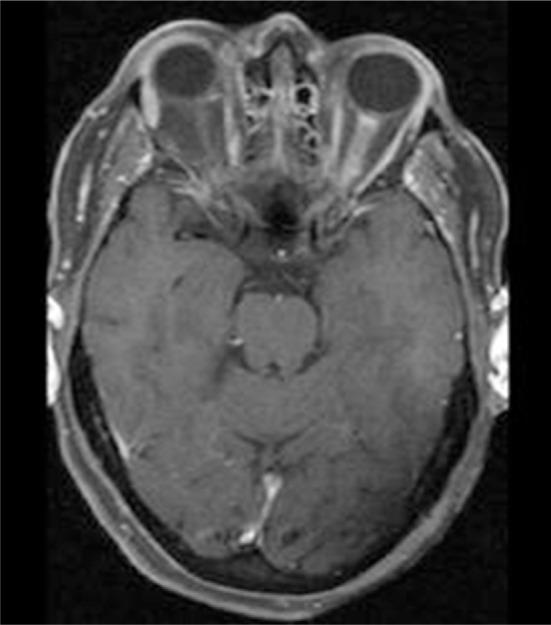

Optic perineuritis (OPN) is a rare inflammatory disorder involving the optic nerve sheath characterized by visual loss. OPN may be isolated and idiopathic or part of an underlying disorder. This case series aimed to help clinicians investigate and manage this disorder. Presentation, clinical findings, and treatment of OPN are discussed. After review of medical records at the ophthalmology clinic at Sahlgrenska University hospital in Gothenburg, Sweden, seven OPN patients (three men and four women) were identified and included in the present case series. These included idiopathic cases and patients with underlying disorders. Age at OPN diagnosis ranged from 26 to 64 years (mean age 55 years, median age 58 years). Five of the patients were treated with corticosteroids. This study suggests that a high-dose course of corticosteroids is important in the treatment of OPN in severely affected patients.

视神经周围炎(OPN)是一种罕见的炎症性疾病,累及视神经鞘,其特征为视力丧失。OPN可能是孤立的、特发性的,也可能是潜在疾病的一部分。本病例系列旨在帮助临床医生对该疾病进行调查和管理。文中讨论了OPN的临床表现、临床发现及治疗方法。在瑞典哥德堡萨尔格伦斯卡大学医院眼科诊所查阅病历后,确定了7例OPN患者(3名男性和4名女性)并纳入本病例系列。这些患者包括特发性病例和患有潜在疾病的患者。OPN诊断时的年龄范围为26至64岁(平均年龄55岁,中位年龄58岁)。其中5例患者接受了皮质类固醇治疗。本研究表明,大剂量皮质类固醇疗程对严重受累的OPN患者的治疗很重要。